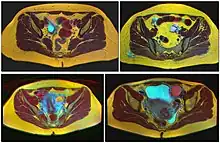

Ovarian cysts are usually diagnosed by ultrasound, CT scan, or MRI, and correlated with clinical presentation and endocrinologic tests as appropriate.[10]